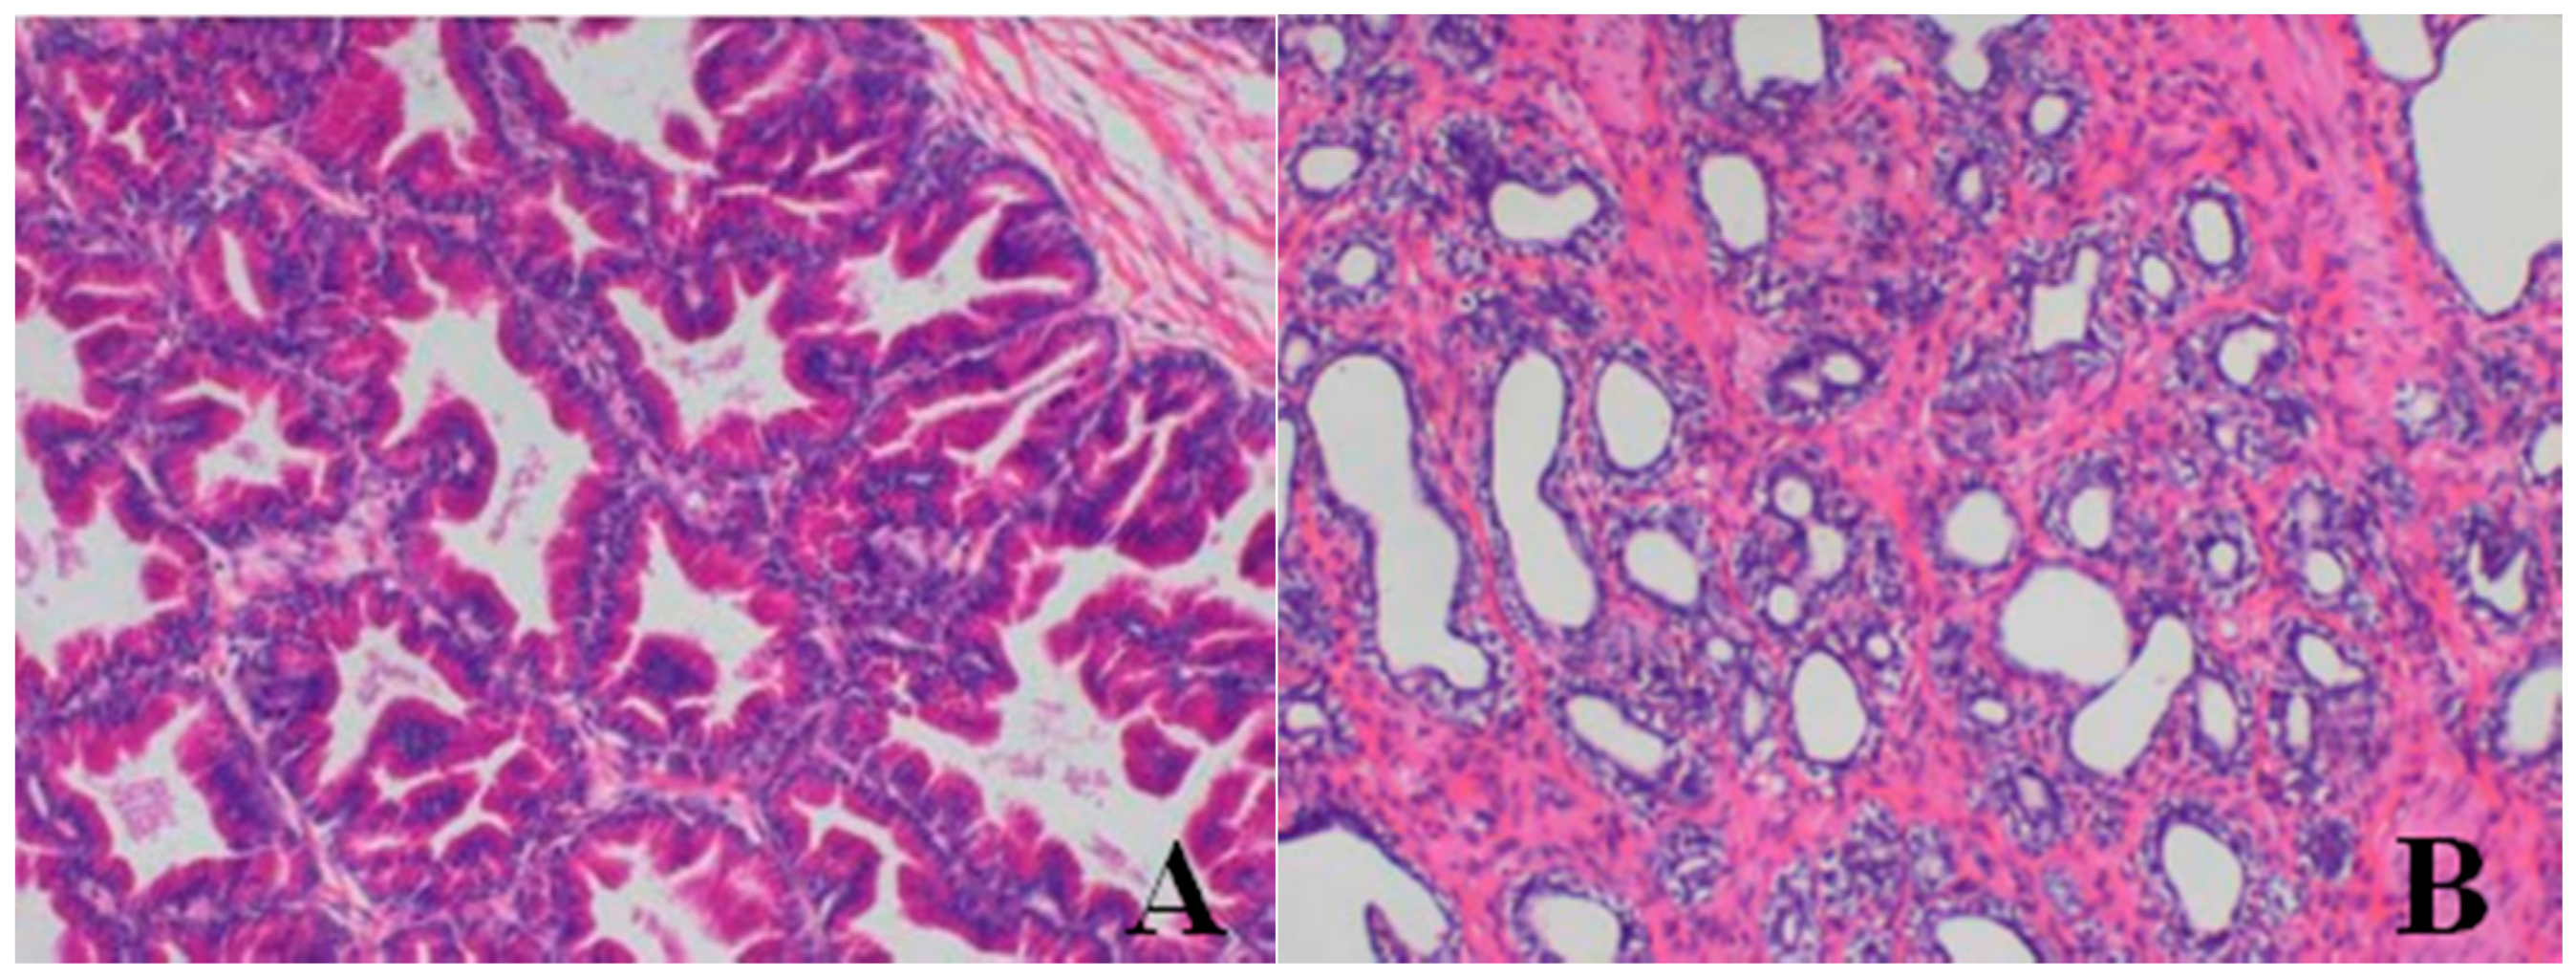

Histopathological Findings

Male reproductive organs (testis, epididymis and prostate)

- Testis: The numbers of seminiferous tubules decreased in dogs belonging to the 80- and 40-mg/kg dose groups, while the tubule lumen decreased and had reduced numbers and types of spermatogenic cells when compared with the control group. Only spermatogonia and some primary and secondary spermatocytes were observed, and there were no mature sperm compared with the control group.

- Epididymis: When compared with the control group, there was a notable lack of mature sperm cells and secretions in the epididymal lumen, as well as a decrease in epididymis lumen size, an irregular shape of the epididymal lumen and an increase in the connective tissue in the interstitium observed in dogs in the 80- and 40-mg/kg dose groups.

- Prostate: When compared with the control group, a reduction in the numbers and size, a thinner epithelium, narrower glandular cavity and increase in the connective tissue in the interstitium were observed in the prostatic acini of dogs in the 80- and 40-mg/kg dose groups.

| Organ | Findings | Dose (mg/kg/day) | ||||

|---|---|---|---|---|---|---|

| 0 | 5 | 20 | 40 | 80 | ||

| Lung | large confluent bronchopneumonia | 0/4 | 0/4 | 0/4 | 2/4 | 2/4 |

| Bone marrow of sternum | decrease in hematopoietic cell numbers | 0/4 | 0/4 | 0/4 | 2/4 | 3/4 |

| Testis | Reduction in numbers and types of spermatogenic cells | 0/2 | 0/2 | 0/2 | 2/2 | 2/2 |

| Epididymis | lack of mature sperm and secretions in the epididymal lumen as well as decrease of epididymal lumen size | 0/2 | 0/2 | 0/2 | 2/2 | 2/2 |

| Prostate | reduction in numbers and size, thinner epithelium, narrowing of the glandular cavity of prostatic acini | 0/2 | 0/2 | 0/2 | 2/2 | 2/2 |